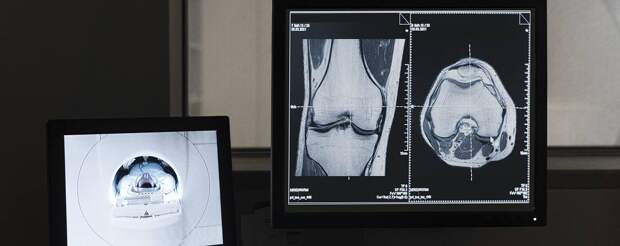

Магнитно-резонансная томография (МРТ) является высокоинформативным методом диагностики заболеваний и повреждений коленного сустава. Процедура позволяет получить детальные изображения мягких тканей, хрящей, связок, сухожилий и костей, что обеспечивает возможность выявления патологических изменений на ранних стадиях развития заболевания.